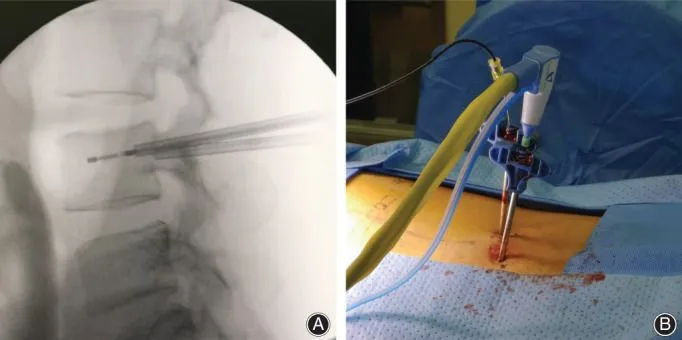

Surgical procedure showing needle insertion with accompanying X-ray guidance.

Step 2: Bore Hole Into Pedicle Bone

A drill is used to bore a hole through the normal pedicle bone of the vertebra.